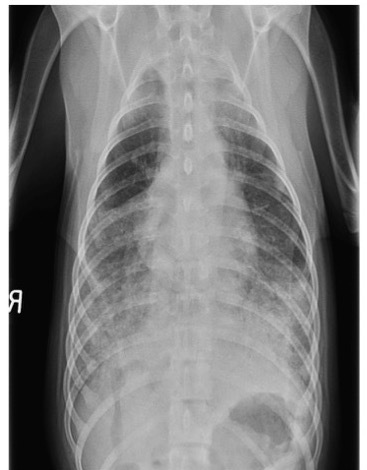

Q

Which lung pattern is shown here?

A

Alveolar pattern

There is characteristic border obliteration